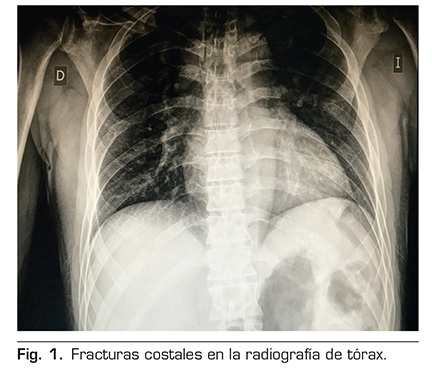

A la exploración física presentaba unas cifras de tensión arterial 150/90 mmHg, saturación arterial de O2 de 96 % al aire ambiente, murmullo vesicular conservado, no focalidad neurológica y dolor importante a la palpación de la pared costal izquierda. En los estudios de imagen realizados se evidenciaron múltiples fracturas costales en el hemitórax izquierdo, desde la 6.ª a la 9.ª costillas, sin evidencia de afectación pleuropulmonar aguda (Figura 1).